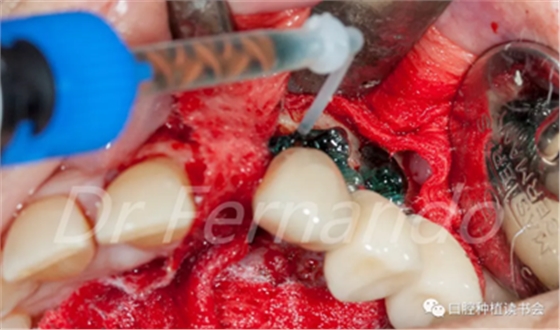

在種植體周圍放置無菌敷料以保護周圍的骨壁和軟組織;用生理鹽水濕潤改善粘附性。用注射器將37%磷酸和2%洗必泰組成的凝膠涂抹在整個種植體表面,讓凝膠作用2分鐘,以促進種植體表面生物膜的分解(圖13 )。

圖13 使用磷酸與洗必泰混合凝膠去除生物膜